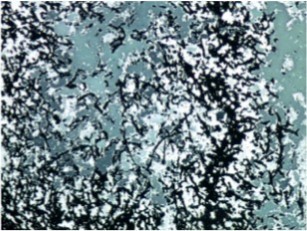

A 64-year-old lady presented to the outpatient department with complaints of headache and right eye blurring of vision for one month. Neurological examination revealed that bitemporal hemianopsia and impairment of visual acuity. Findings from fundus examination were within normal limits. Rest of the brain appeared unremarkable. Endocrine evaluation was normal. Results of renal function tests, liver function tests and haemogram test were within normal limits. A clinical diagnosis of non-secretory pituitary adenoma was made. Magnetic resonance imaging showed a well-circumscribed contrast-enhancing lesion in the sella (Figure 1, Figure 2). The patient underwent an endoscopic endonasal/transsfenoidal surgery in the supine position and total lesion resection was peformed. Intraoperatively, the lesion was found to be yellow colour, soft and avascular and it was removed totally until the sella turcica was visualized (Figure 3).In histopathologic examination septate hyphae were observed between inflammatory cells, Grocott staining is positive, but acid-fast stain for acid-fast bacilli (AFB) was negative. Histopathological findings suggest that infection of Actinomyces (Figure 4, Figure 5). We performed to patient consulted by patients to infectious diseases clinic. Patients underwent intravenous 6x2 gr ampicillin for four weeks.Then oral 4X500 mg amoxicillin treatment is planned a for at least 6 months. Patient did not have any deficits in the next six months.

Figure 5.Grocott stain with filamentous branching bacteria at 10x magnification